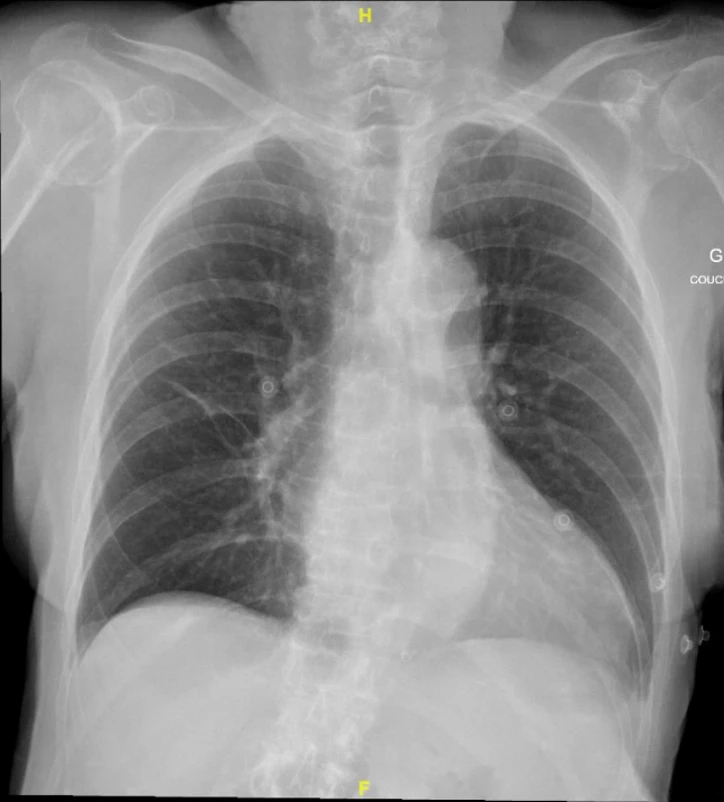

Madame X est une patiente de 89 ans, connue pour une démence, qui se présente aux urgences avec une baisse de l’état général depuis une semaine. Elle décrit une dyspnée d’effort et une légère toux. Le reste de l’anamnèse par système est non contributive, elle ne rapporte notamment pas de chute récente. L’examen clinique n’est pas relevant hormis une désaturation à 91% à l’air ambiant. Le bilan biologique révèle un syndrome inflammatoire, une absence de cinétique des troponines, des D‑dimères dans la norme pour l’âge et un NT-pro-BNP dans la norme. L’ECG ne montre pas de modifications. La radiographie (Rx) du thorax ne révèle pas de signe de surcharge ni d’infiltrat mais elle révèle autre chose : une fracture multi-fragmentaire sous capitale de la tête humérale à droite.

• Qualité du cliché (Symétrie, pénétrance, centrage, inspiration, Debout/​couché)​

• Analyse de la Rx sous le format ABCDEF :

◦ A : Airways (Voies aériennes)

◦ B : Bones (Os)

◦ C : Cardiomediastinal silhouette

◦ D : Diaphragm

◦ E : Extended Lungs/​Everything else (Tout le reste)

◦ F : Foreign bodies (Corps étranger)